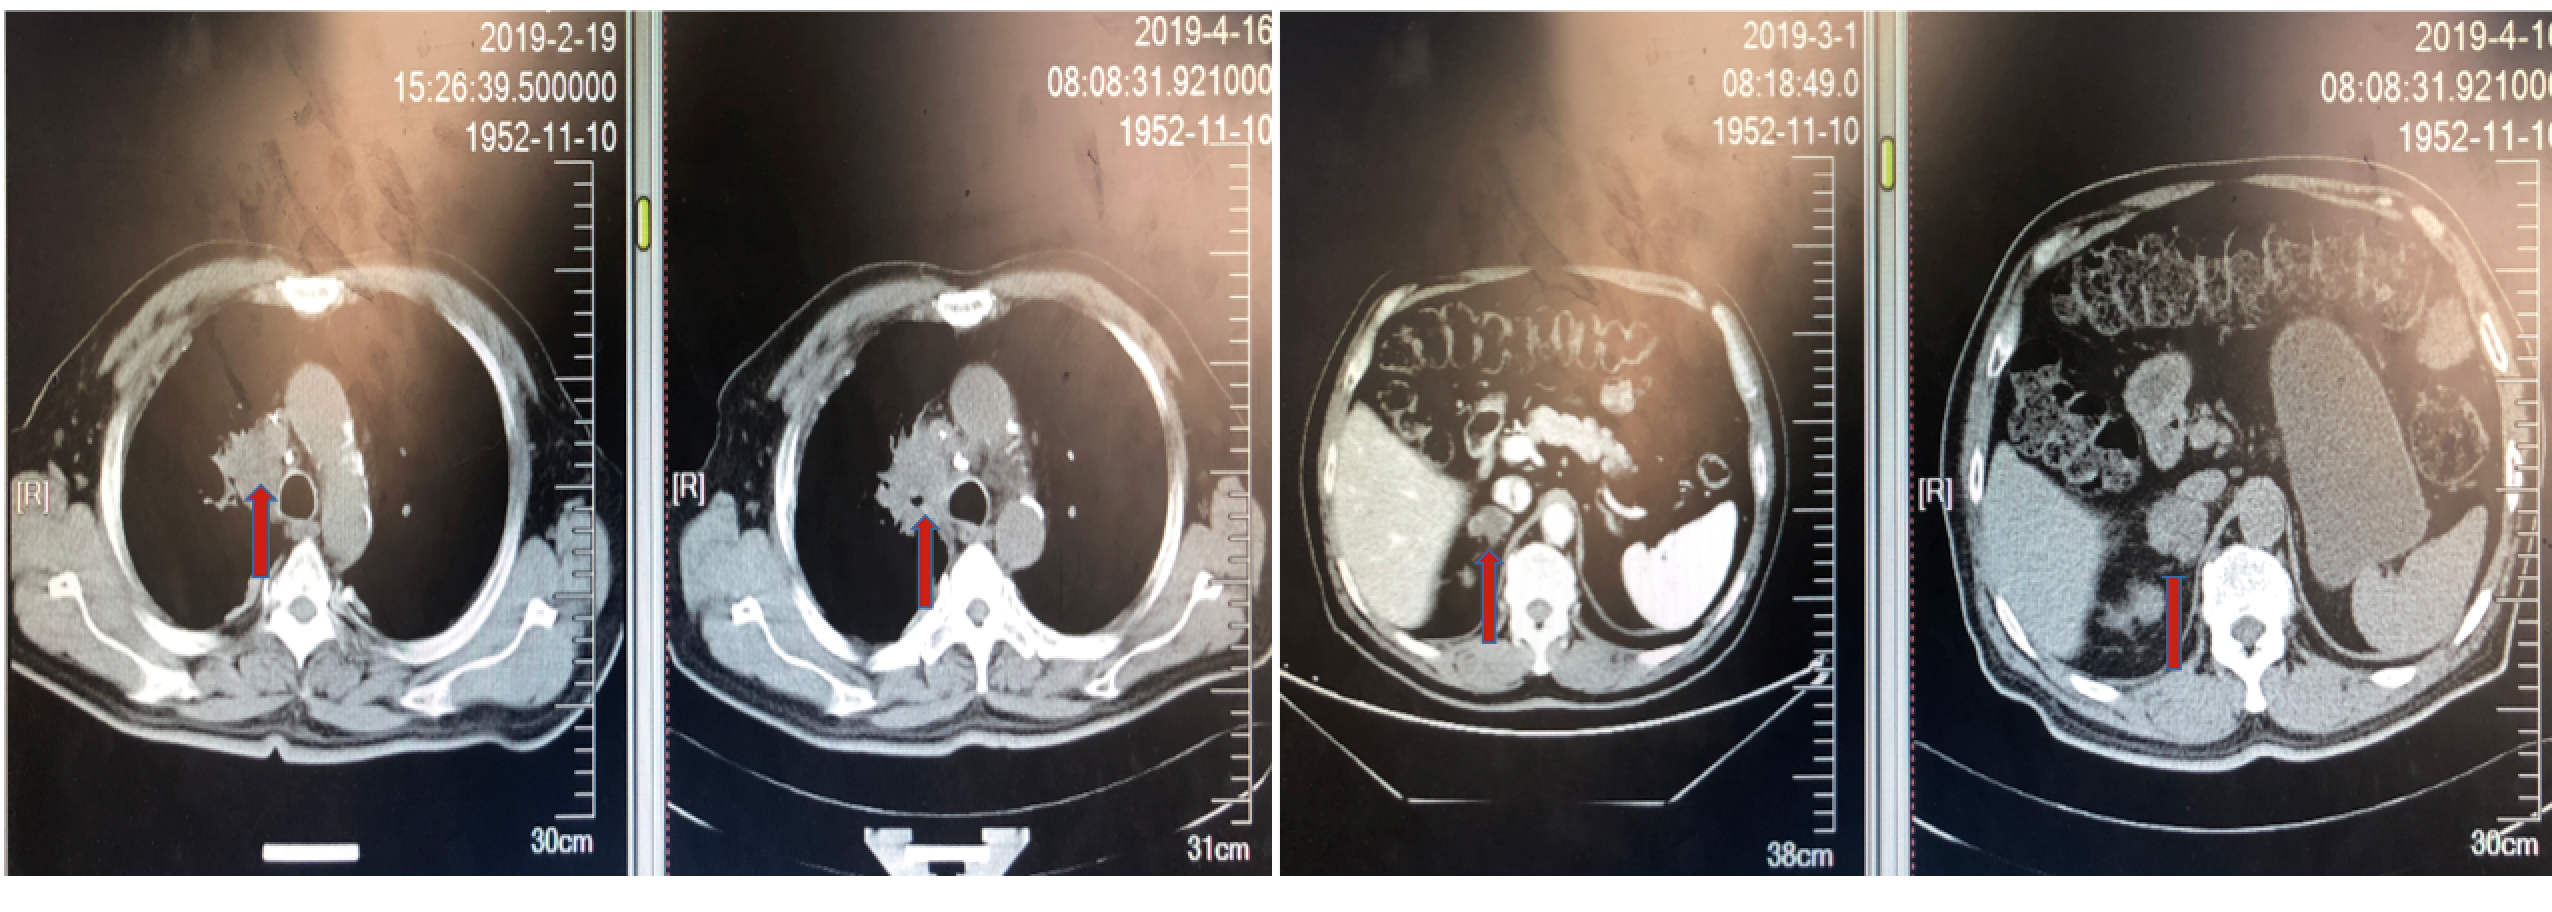

三线治疗前行基因检测,未观察到有意义的驱动突变,PD-L1高表达,>50%; TMB 高,为27.4Mut/Mb。与患者商量后,患者选择信迪利单抗。2019年5~6月接受三线信迪利单抗治疗,方案为信迪利单抗200mg,q21d x 3周期,同时接受唑来膦酸抗骨转移治疗。信迪利单抗治疗3周期后,咳嗽咳血基本消失,仍有腰部疼痛但较前减轻。对治疗耐受良好。复查胸腹部CT:肺部病灶明显缩小,右肾上腺病灶缩小,腰椎病灶变化缓解。目前,患者已经接受信迪利单抗注射液200mg单药治疗第八个周期,体能状态良好,病情改善明显。

图7. 信迪利单抗治疗3周期后肺部病灶明显缩小

图8. 信迪利单抗治疗3周期后肾上腺肿物缩小

图9. 信迪利单抗治疗3周期后腰椎骨转移缓解